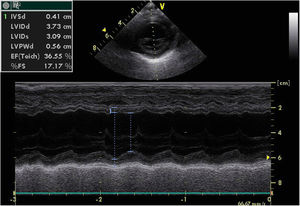

A chest X-ray revealed cardiomegaly with no pulmonary congestion. An electrocardiogram showed sinus rhythm, normal QRS axis, no pathological Q waves and inverted T wave in LI, LII and LIII. An echocardiography found dilatation of the left chambers with global left ventricular dysfunction, left ventricular ejection fraction (LVEF) 36%, left ventricular systolic function (LVSF) 17% and moderate mitral insufficiency, with coronary arteries of apparently normal origin (Figure 1).